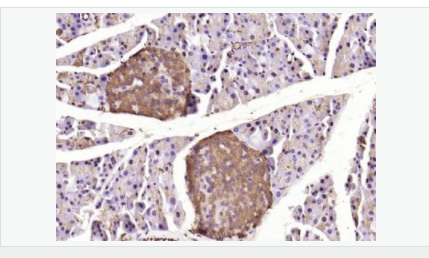

| 產(chǎn)品應(yīng)用 | WB=1:500-2000 ELISA=1:5000-10000 IHC-P=1:100-500 IHC-F=1:100-500 Flow-Cyt=1ug/Test ICC=1:100 IF=1:100-500 (石蠟切片需做抗原修復(fù)) not yet tested in other applications. optimal dilutions/concentrations should be determined by the end user. |

| 產(chǎn)品介紹 | Caspase 9 (also known as ICE like apoptotic protease 6 (ICE LAP6), apoptotic protease Mch6, and apoptotic protease activating factor 3 (Apaf3)) is a member of the peptidase family C14 that contains a CARD domain. This caspase is active as a heterotetramer and has been reported to have two isoforms. ProCaspase 9 has been reported to be approximately 47 kD. This caspase is present in the cytosol and, upon activation, translocates to the mitochondria. Caspase 9 is involved in the caspase activation cascade responsible for apoptosis execution and cleaves/activates Caspase 3 and Caspase 6. Caspase 9 is inhibited by the dominant negative isoform, BclXL, cIAP1, cIAP2, XIAP, and Livin. This caspase becomes activated when recruited to Apaf1/cytochrome c complex, and following cleavage by Apaf1, granzyme B, Caspase 3, possibly Caspase 8 and Caspase 10 into large p37 and small p10 subunits. Caspase 9 intereacts with BIRC7 and has been shown to cleave PARP and vimentin. Function: Involved in the activation cascade of caspases responsible for apoptosis execution. Binding of caspase-9 to Apaf-1 leads to activation of the protease which then cleaves and activates caspase-3. Proteolytically cleaves poly(ADP-ribose) polymerase (PARP). Isoform 2 lacks activity is an dominant-negative inhibitor of caspase-9. Subunit: Heterotetramer that consists of two anti-parallel arranged heterodimers, each one formed by a 35 kDa (p35) and a 10 kDa (p10) subunit. Caspase-9 and APAF1 bind to each other via their respective NH2-terminal CED-3 homologous domains in the presence of cytochrome C and ATP. Interacts (inactive form) with EFHD2. Interacts with HAX1. Interacts with BIRC2/c-IAP1, XIAP/BIRC4, BIRC5/survivin, BIRC6/bruce and BIRC7/livin. Tissue Specificity: Ubiquitous, with highest expression in the heart, moderate expression in liver, skeletal muscle, and pancreas. Low levels in all other tissues. Within the heart, specifically expressed in myocytes. Post-translational modifications: Cleavages at Asp-315 by granzyme B and at Asp-330 by caspase-3 generate the two active subunits. Caspase-8 and -10 can also be involved in these processing events. Phosphorylated at Thr-125 by MAPK1/ERK2. Phosphorylation at Thr-125 is sufficient to block caspase-9 processing and subsequent caspase-3 activation. Similarity: Belongs to the peptidase C14A family. Contains 1 CARD domain. SWISS: P55211 Gene ID: 842 Database links: Entrez Gene: 842 Human Entrez Gene: 12371 Mouse Omim: 602234 Human SwissProt: P55211 Human SwissProt: Q4FJK5 Mouse Unigene: 329502 Human Unigene: 88829 Mouse Unigene: 32199 Rat Important Note: This product as supplied is intended for research use only, not for use in human, therapeutic or diagnostic applications. Caspase-9半胱氨酸蛋白酶家族成員之一,又稱ICE-Lap6(ICE Like apoptotease 6)參與細胞凋亡過程和細胞因子的加工過程,在許多胚胎和成人組織中都有分布。此抗體主要用于腫瘤研究。 |